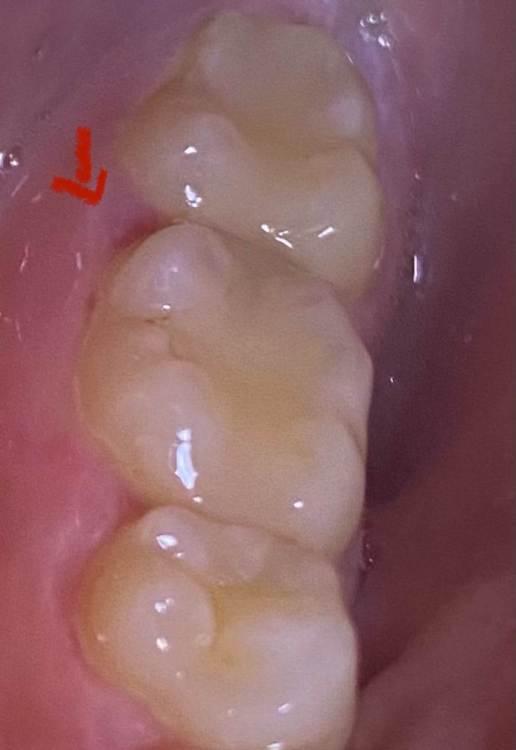

vanessa120 Опубликовано 18 марта, 2023 Поделиться Опубликовано 18 марта, 2023 Недавно появилось легкое пульсирующее ощущение в боковой части лица, иногда я чувствую боль (я думаю) в зубе, но она приходит и уходит, просто чувствует себя немного странно? Не болит при надавливании или что-то в этом роде. Это просто воспаленная десна или что-то более серьезное? Это похоже на карьес, но я не могу позволить себе ходить к стоматологу в данный момент. Очень туго с деньгами. У меня клиническая депрессия, поэтому мое здоровье полости рта не очень хорошее. Какие-нибудь домашние средства, которые могли бы сработать? Я прикрепил фотографии. я не пью и не курю Ссылка на комментарий

shishok Опубликовано 19 марта, 2023 Поделиться Опубликовано 19 марта, 2023 Похоже на вторичный кариес под пломбой. Хорошо бы снимок посмотреть. Кариес лучше полечить побыстрее (может заболеть в любой момент). Ссылка на комментарий